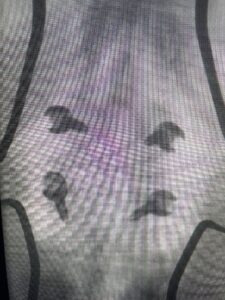

Another patient is a 62 year-old female with progressive low back pain and right leg pain and numbness that radiates to the top of her foot. She tried physical therapy and epidural injections. MRI demonstrated severe L3-4 stenosis and a grade 1 spondylolisthesis (Fig 4). There was L5-S1 and L4-5 disc collapse with modic end-plate changes. Biomechanically because of the significant degeneration of these disc spaces which stiffened the L4-S1 segment more stress was placed on the L3-4 segment, resulting in significant premature degeneration and compensatory stenosis and segmental instability. The MRI also showed pathologically, because of the slip, the L3 inferior processes were more anteriorly oriented and hence contributing to the majority of the lumbar canal compromise. Note the more sagittally-oriented facets in this case compared to the prior case (Fig 5). The patient underwent a decompressive laminectomy with attention of removing the inferior processes of L3 to fully decompress the canal. We also performed an L3-4 fusion with instrumentation (Fig 6). The patient had an uneventful postoperative course with improvement of leg pain. Of note with relief of the disabling leg pain patients are generally very happy. Patients can often manage their low back pain; it is the leg pain that they just can’t tolerate.

Fig 6: AP and lateral fluoroscopic images demonstrating pedicle screw placement in L3-4 fusion for spondylolisthesis.